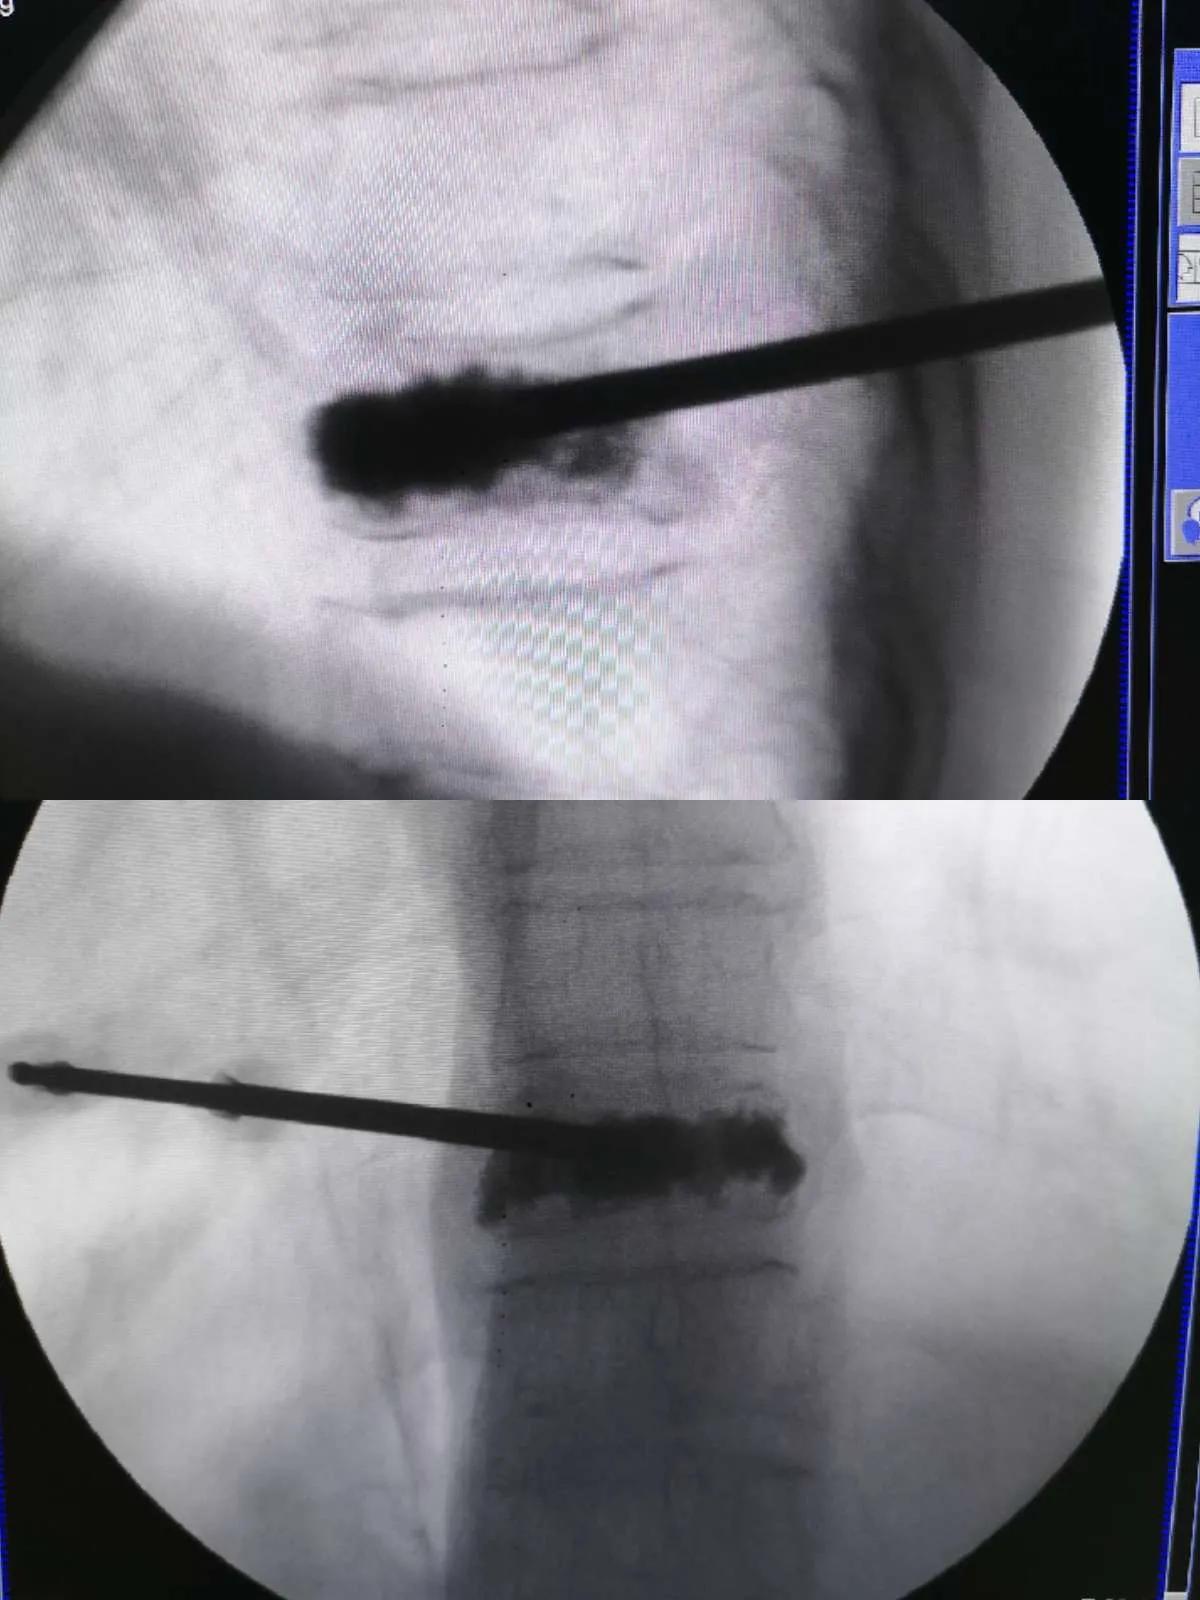

PVP仅仅需要一个0.5CM的小口子,将搅拌好的骨水泥使用专用注射器或者推杆推入压缩的椎体,骨水泥可发热并逐渐凝固,达到使椎体瞬间强化的目的。一般术后患者背痛会明显缓解,术后第二天即可下地行走。

椎体成形术强化胸10椎体

在局麻下手术,仅需骨水泥推杆大小的切口,无需缝合。